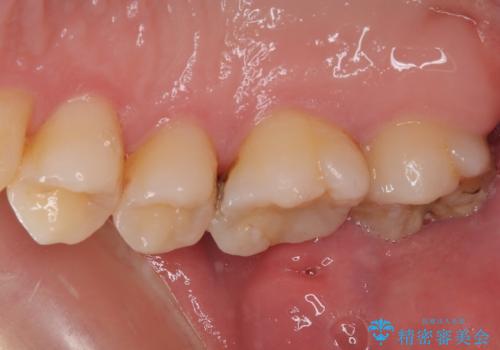

- 他院で矯正治療前後に処置を行った歯が痛むとのことで来院された患者様です。

下顎大臼歯は根管治療がされている歯が咬合時に痛みを感じ、上顎の大臼歯2歯は冷たいものがしみる状態でした。

まずはしみる上顎の歯を仮歯に置き換え、その後下顎の根管治療を行った上で、異常が認められなければオールセラミッククラウンにて補綴治療を行うこととしました。